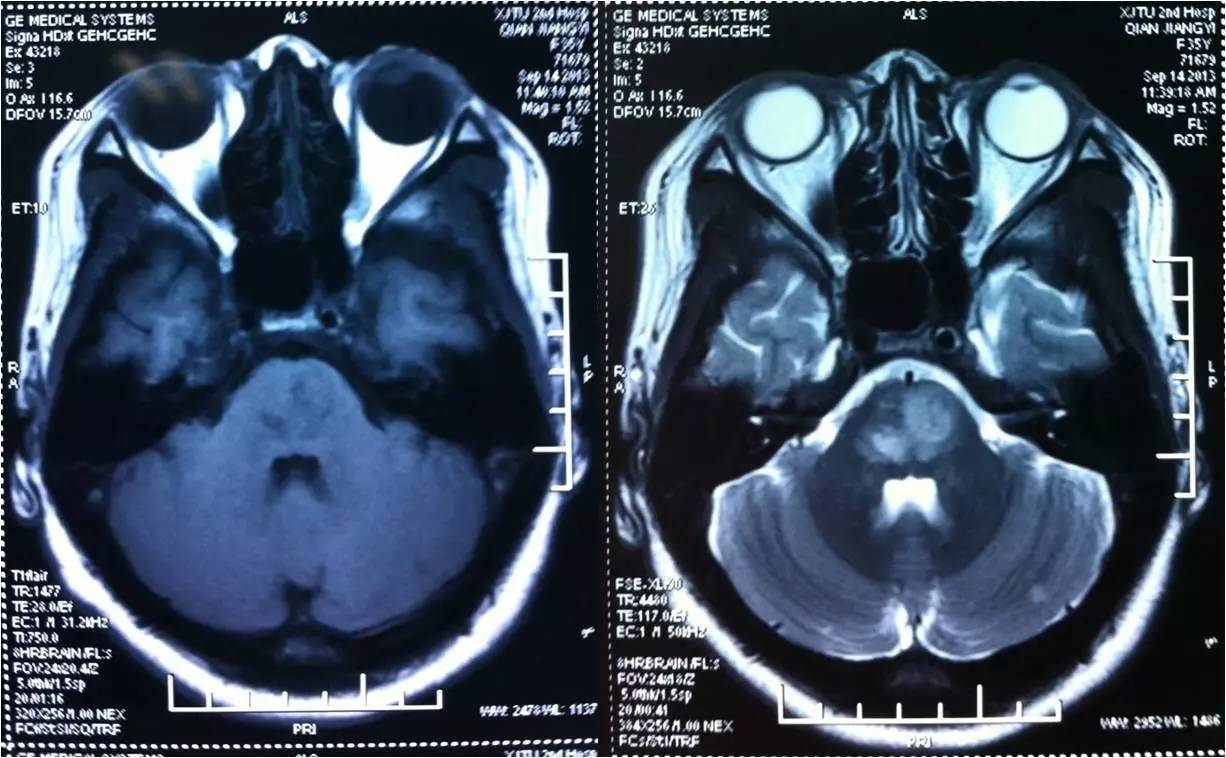

》男性,47岁,SIE;

》UCG:主动脉瓣关闭不全,赘生物;

》突发言语不能、右侧肢体活动不能;

》查体:运动性失语,右侧肌张力低,右侧肌力0级,右侧巴氏征阳性 。NIHSS评分18分;

》CT:颅内未见出血;

》DSA:左侧大脑中动脉闭塞。

术前